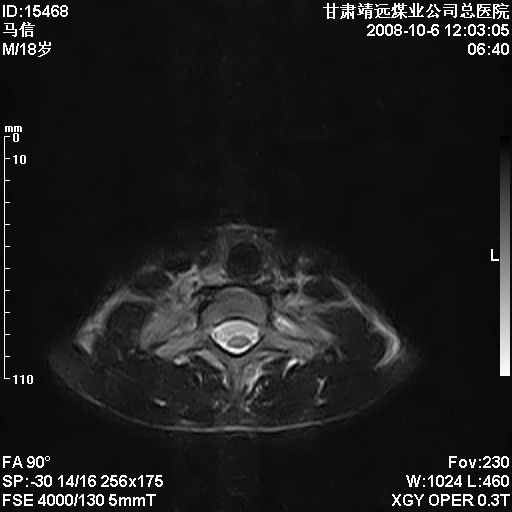

患者18岁,学生,在玩耍中受伤来检查,患者喜欢打篮球。颈椎内异常信号影,我们考虑占位,但是不像占位,又考虑硬膜囊的增厚,大家关建看颈椎椎管内的那个异常占位信号

腰椎的改变是不是正常发育的改变,还是打篮球的长期慢性损伤。

考虑 c3-4 c4-5 c5-6椎间盘突出,l3-4 l4-5 l5-s1椎间盘变性

颈椎建议做增强扫描;腰椎诸椎终板骨骺炎。

脑脊液流动伪影?

后纵韧带增厚,颈2/3、3/4、4/5、5/6椎间盘变性、突出;椎体有旋转,提示椎小关节有问题;腰椎间盘变性,许莫氏结节。

是正常的脑脊液波动伪影

脑脊液流动伪影

你说的占位是伪影。在我们医院1.5t和3.0t的mr上是经常看见的。